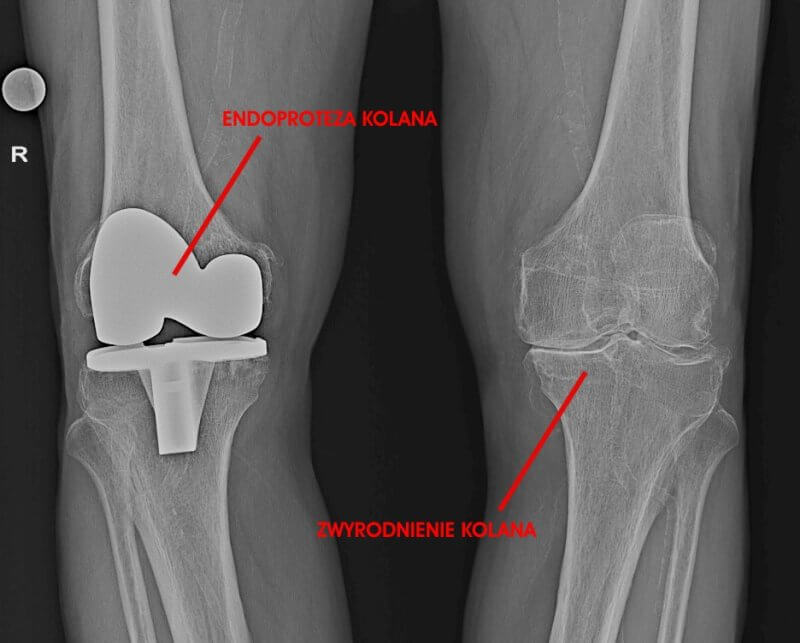

- Diagnostyka: RTG stawów kolanowych w obciążeniu; zwężenie szpary stawowej i osteofity.

Dla potwierdzenia diagnozy ortopeda zleci dodatkowe badania obrazowe. Podstawą diagnostyki choroby zwyrodnieniowej stawu kolanowego jest badanie radiologiczne (RTG stawów kolanowych w obciążeniu). Na zdjęciu rentgenowskim widać zwężenie przestrzeni stawowej (spowodowane utratą chrząstki), obecność osteofitów (narośli kostnych) oraz ewentualne deformacje kości. W ocenie struktur łącznotkankowych, w tym chrząstki, wykorzystuje się również rezonans magnetyczny (MRI), badanie ultrasonograficzne (USG). Po zebraniu wszystkich informacji lekarz ortopeda postawi diagnozę i zaproponuje odpowiednie leczenie.

- Endoprotezoplastyka stawu kolanowego - jest to wymiana stawu kolanowego na sztuczną endoprotezę. Zabieg ten jest zazwyczaj proponowany dla Pacjentów ze zwyrodnieniem kolana na zaawansowanym etapie, którzy nie reagują na inne metody leczenia.